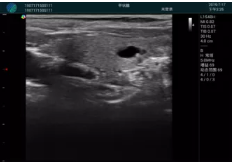

可視化甲狀腺穿刺引導(dǎo)

甲狀腺囊性結(jié)節(jié),囊壁鈣化,透聲好

甲狀腺囊性占位

2001年美國健康護理研究和質(zhì)量監(jiān)督局(AHRQ)批準了一項關(guān)于提高患者安全性的報告,建議:在頸內(nèi)靜脈中心置管術(shù)時使用超聲引導(dǎo)。此后超聲引導(dǎo)穿刺被用于幾乎所有的急診穿刺操作,尤其是血管穿刺。

便攜超聲在急診穿刺中的應(yīng)用: